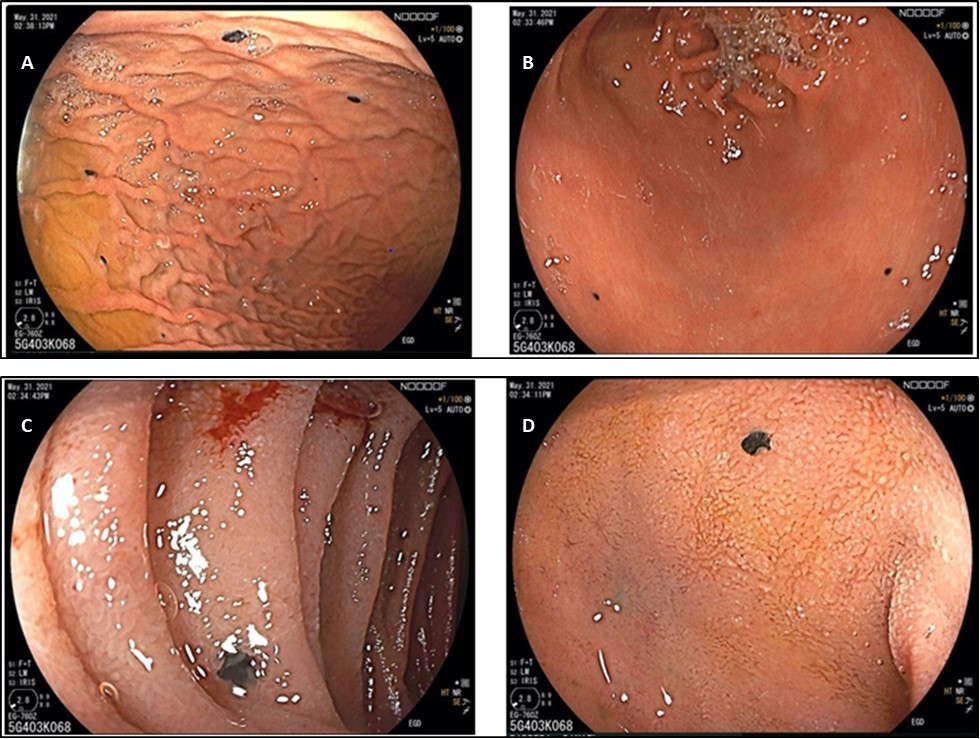

In the interim, he had an esophago gastroduodenoscopy which showed multiple flat lesions seen at the body (Figure 1a), antrum (Figure 1b) and at the duodenum (Figure 1c and 1d). Biopsy samples were taken and they showed epithelial cells disposed singly and in nests invading the gastric mucosa. These biopsy findings were consistent with malignant melanoma. Besides melatonin nodules, only erosive gastritis with no ulcers was noted.

Figure 1.(A) Antrum (B) Gastric body (C) 2nd part of the Duodenum (D) Duodenal bulb

Concerning the anatomic site of gastric metastases, the majority of these are reported to occur in the body and in the fundus of the stomach, most often in the greater curvature with lesions in the lesser curvature being very uncommon3. In our patient the lesions were located at the body (Figure 1A), and at the antrum (Figure 1B), as also seen at the duodenal bulb and the second portion (Figure 1C and 1D). CT scans showed metastases noted on the lungs, mediastinal lymph nodes and right hepatic lobe.

The endoscopic classification of gastric metastases comprises three main morphological types. First, melanotic nodules often have an ulcerated tip. Secondly, there are submucosal tumor masses which are elevated and ulcerated at the apex. Third, morphological type is a mass lesion with varying incidence of necrosis and melanosis. In our patient he had the first morphological type3, 4.